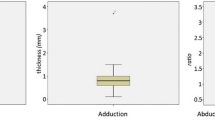

Bursa subacromialis and subdeltoidea

The inter-observer variability for the maximum width of the subacromial and subdeltoid bursa was very strong in a coronal (subdeltoid bursa: ICC = 0.921; p < 0.001; subacromial bursa: ICC = 0.978; p < 0.001) and sagittal plane (subdeltoid bursa: ICC = 0.942; p < 0.001; subacromial bursa: ICC = 0.949; p < 0.001).

The width of the subacromial bursa measured in a coronal plane was negatively correlated with the mean (r = −0.340; p = 0.004) and maximum abduction force (r = −0.311; p = 0.009). The mean abduction force was negatively correlated with the width of the subacromial bursa measured in a sagittal plane (r = −0.253; p = 0.036).

The width of the subdeltoid bursa measured in a coronal plane was positively correlated with shoulder pain (r = 0.248; p = 0.004), negatively with range of abduction (r = −0.27; p = 0.025), mean (r = −0.332; p = 0.005) and maximum abduction force (r = −0.334; p = 0.005). When measured in a sagittal plane, a positive correlation was observed only with shoulder pain (r = 0.330; p = 0.006) but not with range of abduction, mean and maximum abduction force.

Shoulder pain had the strongest correlation with the width of the subdeltoid bursa measured in a coronal plane. Therefore, the width of the subdeltoid bursa measured in a coronal plane seems to be a feasible parameter to assess shoulder function in patients with primary extrinsic shoulder impingement. This hypothesis is further supported by the regression analysis in which the width of the subdeltoid bursa measured in a coronal plane was the only MR imaging parameter that could significantly predict the Constant Score, mean and maximum abduction force, shoulder pain and the range of abduction (see Table 2). This is not surprising since the maximum width of each bursa can be interpreted as an indicator of bursitis. A possible connection of both bursae, whose presence is still in debate [26], could explain the significant correlation of the maximum width of both bursae. Another explanation could be that bursitis of both bursae seems to occur together.